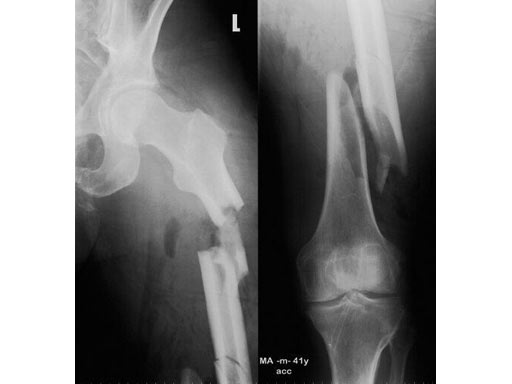

41- year- old male; accident with a motorbike.